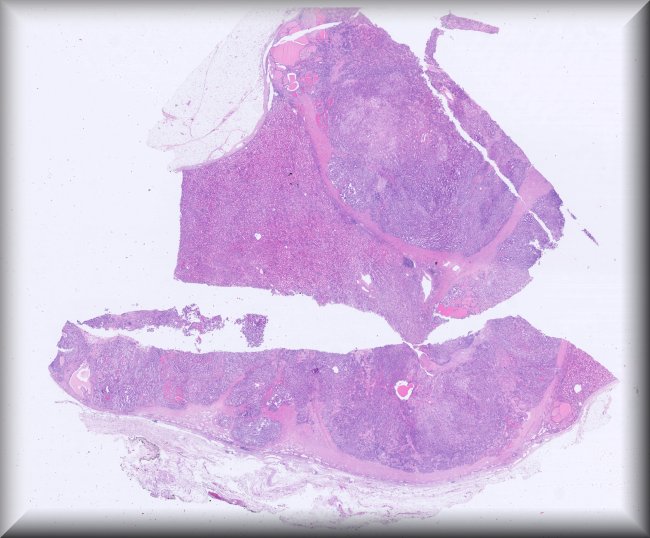

Tumor testicular en paciente de 85 años: Varón de 85 años con antecedentes de riesgo cardiovascular (HTA, dislipemia, IMA hace más de 20 años, fibrilación auricular desde 2018) y antecedentes oncológicos de adenocarcinoma de sigma y próstata.El paciente ha estado en seguimiento desde 2017 por adenocarcinoma de próstata Gleason 7 (3+4), con invasión perineural y afectación ganglionar retroperitoneal. Fue tratado con radioterapia y bloqueo androgénico intermitente. En noviembre de 2023, un PET-TAC mostró recaída ganglionar ilíaca izquierda y actividad intensa en la bolsa testicular izquierda.